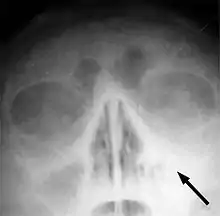

Normalt vil bihulebetændelsen aftage af sig selv efter 4-5 dage og kan lindres ved almindeligt smertestillende håndkøbsmedicin, men kan ellers behandles med penicillin. For patienter, der får bihulebetændelse flere gange, kan det være formålstjenstligt at røntgenfotografere bihulerne for at kunne konstatere hvorvidt slimhinderne i bihulen er normale.